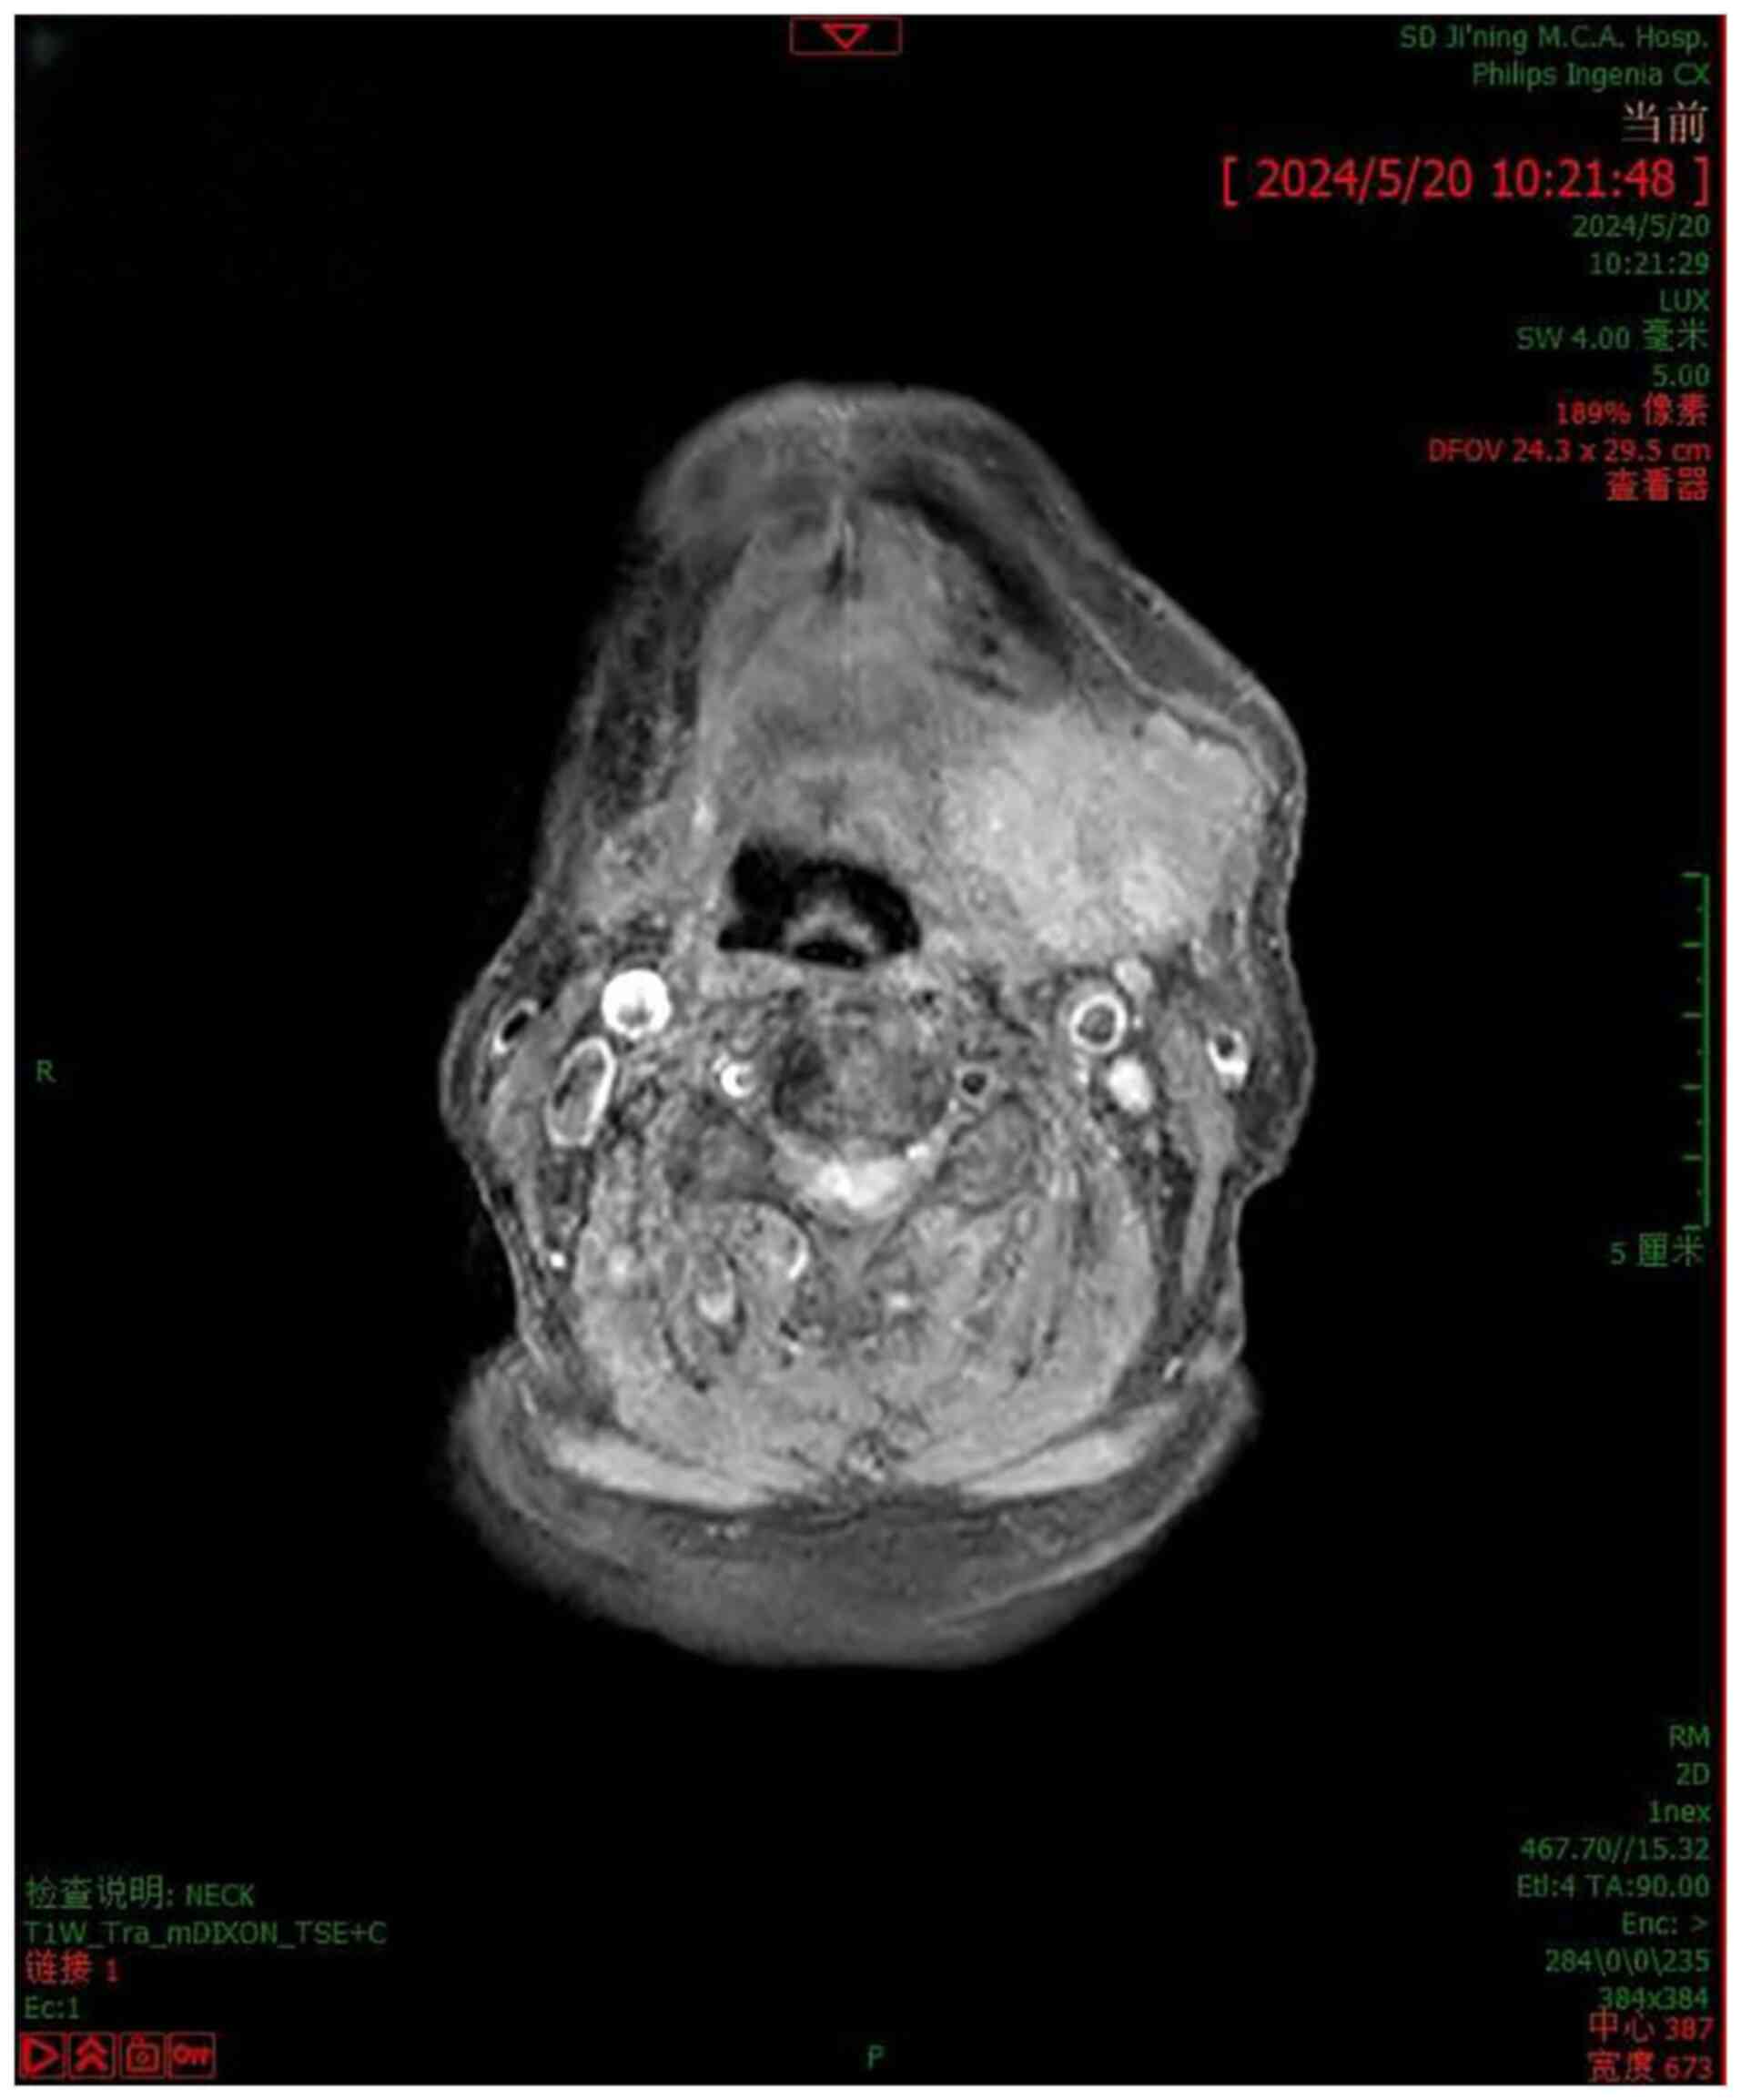

Myoepithelial carcinoma (MEC) is a malignant tumour composed almost entirely of cells differentiated from the myoepithelium. It is rare, most commonly occurring in the parotid gland. In the current study, a rare case of MEC in the submandibular gland was presented. An 82‑year‑old male patient was admitted with a swelling in the upper left neck that had been present for 60 years. Magnetic resonance imaging indicated a tumour in the region of the left submandibular gland, which was not easy to clearly distinguish from the gland itself and an enhancement scan was recommended but not performed. Furthermore, multiple lymph nodes of varying sizes were present in the submandibular region of the neck on both sides. These enlarged lymph nodes had signs of involvement. Accordingly, a surgery was performed. The pathological diagnosis indicated the presence of a malignant tumour in the left upper neck. The tumour was most likely an MEC with pleomorphic adenoma, based on the results of immunohistochemistry. The size of the tumour mass was 5x5x4 cm. Histology indicated that the tumour cells exhibited infiltrative growth, with a sparse arrangement and a predominance of hyaline and spindle‑shaped cells. In certain regions, the tumour tissue displayed characteristics similar to pleomorphic adenoma. The results of the immunohistochemical analysis were as follows: CD31(‑), CD34(‑), cytokeratin (CK)7 (+), vimentin (+), Ki‑67 (+, 70%), erythroid growth factor receptor (‑), desmin (‑), anaplastic lymphoma kinase (‑), P40 (+), CK pan‑antibody (+) and epithelial membrane antigen (‑). The patient underwent a surgical procedure to remove the lesion in the neck under sedation with complex anaesthesia. The sample excised from the surgery was sent to the pathology department for diagnosis. Given the high recurrence frequency of MEC, monitoring patients closely after surgery is crucial.